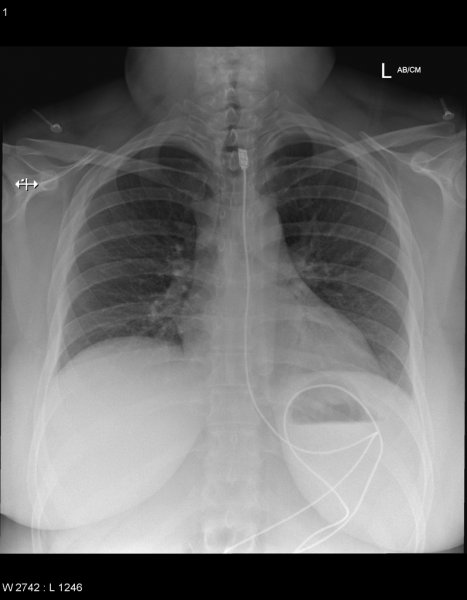

Специалисты по рентгеновской диагностике регулярно сталкиваются с посторонними предметами внутри тела человека. Обычно лишние предметы попадают в пищеварительную систему из-за неосторожности при еде или во время неудачных любовных игр. Почти всё удается вытащить — с хирургическим вмешательством или без него. выбрал самые необычные находки радиологов, которыми они делились на сайте Radiopaedia.org.